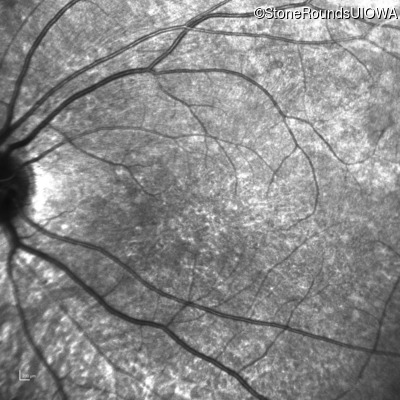

Age at visit: 8 years

OD OS

This 8 year old girl had normal vision until age 6 when she failed a school vision screening. That year, she was able to play softball well, but this year she often loses sight of the ball and is often hit by it.